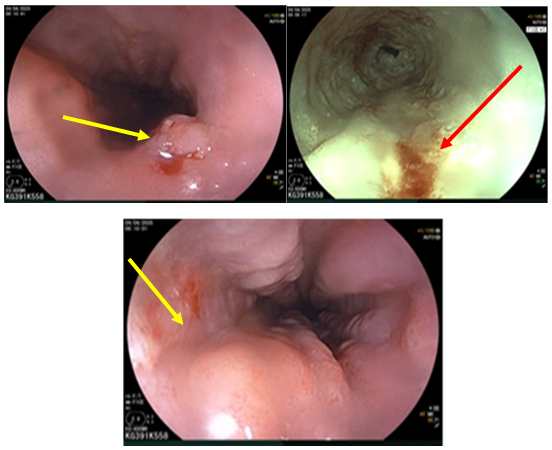

- Nội soi thực quản (Tháng 03/2025): Cách cung răng trên 40cm có đám niêm mạc khác màu kích thước ~ 3cm (sinh thiết ống 1). Cách CRT 38cm có đám thứ 2 kích thước ~ 2cm (sinh thiết ống 2). Cách cung răng trên 25- 30cm có đám niêm mạc gồ ghề, khác màu chạy vòng gần hết chu vi (sinh thiết ống 3). Hạ hầu có sẹo và nhiều đám loạn sản mạch (sau xạ trị). Dạ dày: viêm dạ dày. Kết luận: Tổn thương loạn sản thực quản (3 vị trí) – viêm dạ dày – tổn thương hạ hầu sau xạ trị.

Hình 4: Nội soi thực quản hình ảnh tổn thương nhiều vị trí (mũi tên vàng và đỏ)